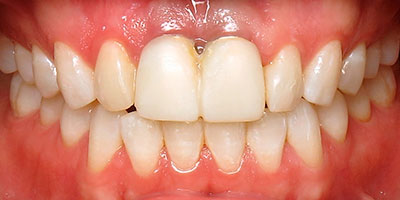

Paciente femenino de 30 años de edad, se presenta en el consultorio en incisivos centrales superiores, férula de alambre y acrílico. El tiempo de evolución es de 6 días después de sufrir una caída, causando la avulsión de sus dientes incisivos centrales, la trataron y colocaron los dientes dos días posterior al accidente.

Dientes Ferulizados